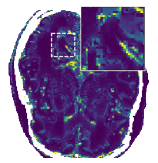

Figure 5 shows an example of a spatio-temporal regularization parameter-map which was estimated using the proposed approach for an acceleration factor of . The network estimates the regularization parameter-map to be pointwise relatively consistenly higher than the spatially required regularization. This result is in fact expected as the temporal dimension is the one for which the gradients of the images are the sparsest because of the high temporal correlation. Further, we see how the network consistently predicts both the spatial regularization as well as the temporal regularization to be less strong in the area where most of the movement is expected, i.e. in the cardiac region.

Figure 6 shows examples of the quantitative (magnitude) images of three of the 112 simulated inversion recovery measurements in the test dataset. We also show the regularization parameter-maps for regularization along the spatial directions and along the inversion-time direction generated by the network. The mean PSNR and SSIM of our proposed method is consistently higher for all considered acceleration factors, even compared to PDHG with regularization strength along spatial and inversion-time direction chosen by grid-search with access to the ground truth images (shown in Figure 8 and Table 2). The resulting parameter-maps after performing the regression on the reconstructed images are shown in Figure 7. Again, our proposed method results in the lowest RMS deviation from the ground truth images (Table 2).